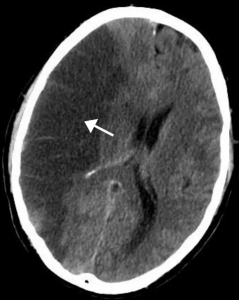

A stroke can happen suddenly and without warning. According to Healthline, a stroke occurs when blood flow to part of the brain is blocked, causing brain cells to begin dying within minutes.

Because time is critical, getting medical help quickly can make the difference between full recovery and long-term disability.